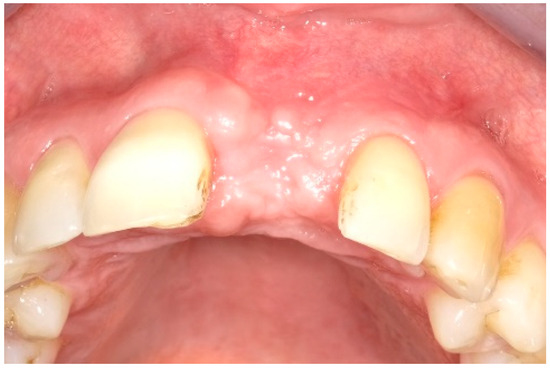

6. Follow-Up

| Midfacial mucosa level at Tpre (mm) | 3.0 | 2.0 | 5.0 |

| Midfacial mucosa level at T9 (mm) | 5.0 | 6.0 | 6.0 |

| Midfacial mucosa level at T12 (mm) | 5.0 | 6.0 | 6.0 |

| Midfacial keratinized tissue width at Tpre (mm) | 3.0 | 7.0 | 5.0 |

| Midfacial keratinized tissue width at T9 (mm) | 3.0 | 3.0 | 3.0 |

| Midfacial keratinized tissue width at T12 (mm) | 3.0 | 3.0 | 2.0 |

| Mesial papilla | 1 | 1 | 0 | 0 | 2 | 2 |

| Distal papilla | 1 | 1 | 0 | 0 | 2 | 1 |

| Curvature of the facial mucosa | 1 | 1 | 2 | 2 | 1 | 2 |

| Level of the facial mucosa | 0 | 2 | 2 | 1 | 1 | 2 |

| Root convexity/soft tissue color and texture | 0 | 1 | 2 | 2 | 0 | 1 |

| Total | 3 | 6 | 6 | 5 | 6 | 8 |